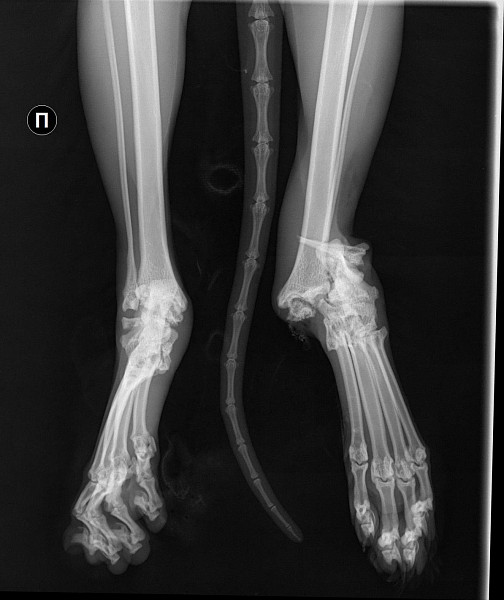

Рентгеновские снимки перелома лапы у кота: диагностика и лечение